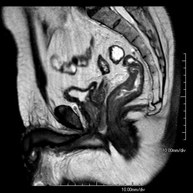

Prova diagnòstica no invasiva que consisteix en l'obtenció d'imatges d'alta definició anatòmica de la pelvis mitjançant l'ús d'un camp electromagnètic i ones de ràdio (amb un emissor i un receptor). No utilitza radiació ionitzant. Es realitza per a l'estudi de patologies d'úter, d'ovari, de trompes i de vagina, ja siguin d'origen tumoral, inflamatori o vascular. També permet valorar les estructures adjacents localitzades a la pelvis i la identificació de les seves alteracions. De vegades és necessari l'ús de contrast intravenós (Gadolini) per caracteritzar les lesions. - RM Pelvis masculina

Prova diagnòstica no invasiva que consisteix en l'obtenció d'imatges d'alta definició anatòmica de la pelvis masculina mitjançant l'ús d'un camp electromagnètic i ones de ràdio (amb un emissor i un receptor). No utilitza radiació ionitzant. No requereix preparació prèvia. En algunes ocasions necessita l'ús de contrast paramagnètic (Gadolini) per caracteritzar les lesions. Aquesta prova permet valorar òrgans com la bufeta urinària, la unió entre els urèters i la bufeta, la pròstata, les vesícules seminals, la uretra i els ossos de la pelvis, entre d'altres. - RM de Fetge